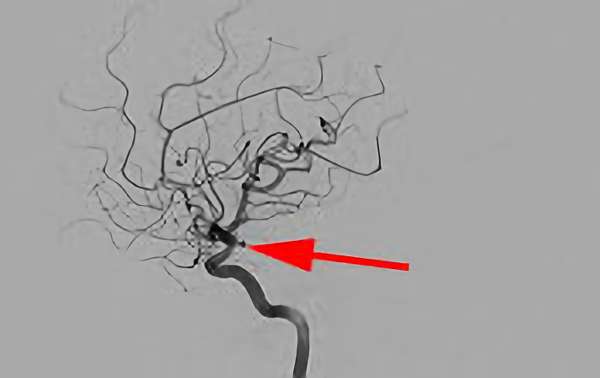

No.1631 手術前